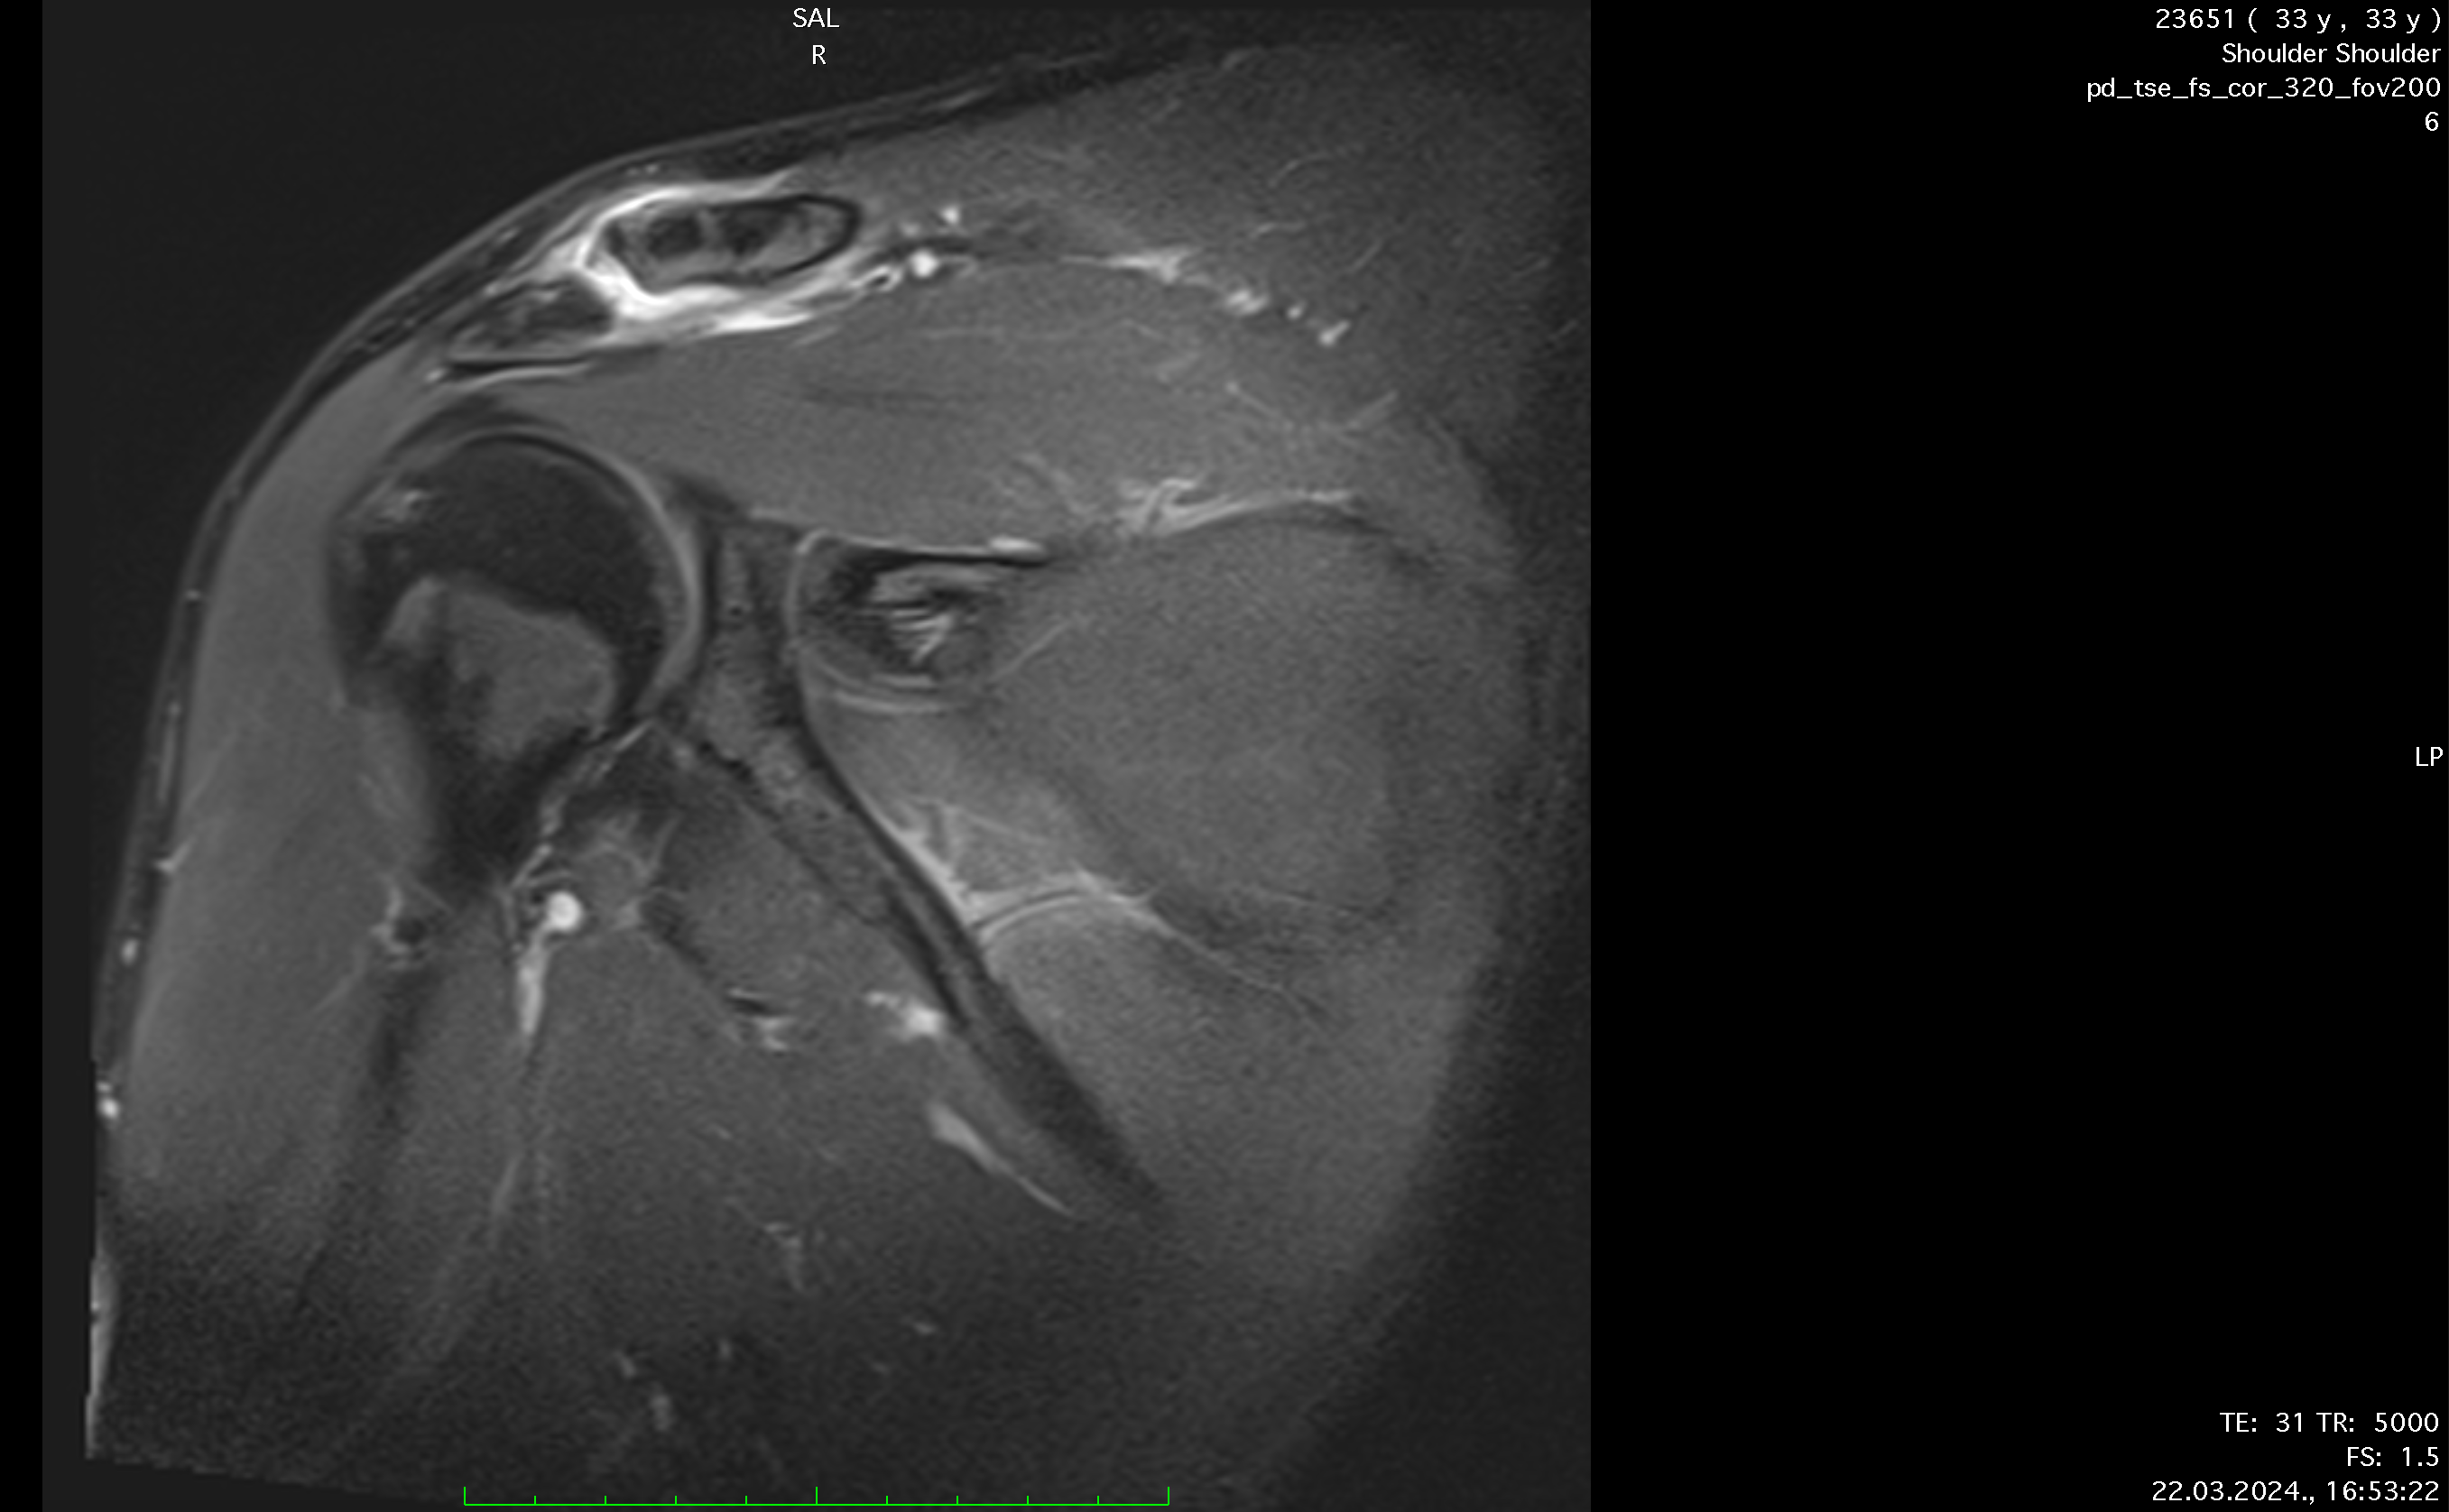

Ten days after the injury, the player's pain level had decreased to 3 out of 10, and nearly full ROM had been regained. A follow-up MRI showed significant recovery, with the AC joint fully reconnected and healed ligaments, though there was some residual edema caused by inflammation from the prolotherapy. Treatment continued for another week, during which the player engaged in more active exercises, including mobility, weight-bearing, and rotator cuff strengthening. While fast movements initially caused stiffness, this resolved within 3 to 4 days.

Reconnection of coracoclavicular ligament, soft tissue, trapezius m., regeneration, formation of AC joint capsule visible after only 8 days of therapy.